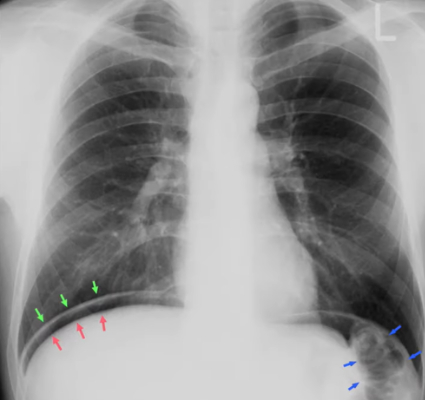

The red arrows indicate the upper border of the (BLANK).

B) Liver

C) Air fluid level

A) Intestinal walls

B) Inner and outer layers of the intestine